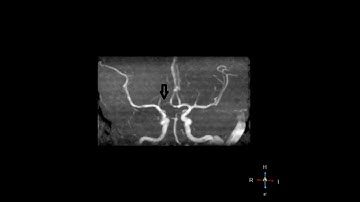

Fetal PCOM/PCA and Aplastic A1